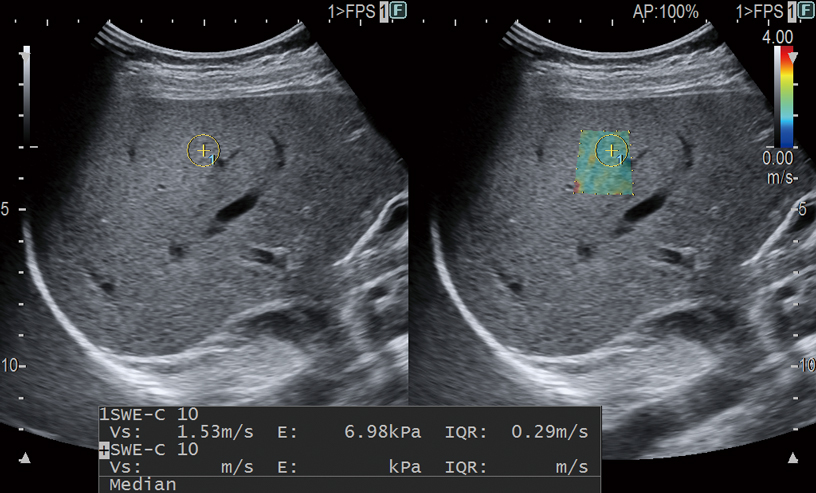

Avoid complex procedures like biopsy or MRI with our easy-to-use shear wave ultrasound features. Shear waves are generated using a ‘push pulse‘ to excite the tissues. SWM provides an assessment of tissue stiffness by calculating Vs, the propagation velocity of the shear waves. Thank to our unique reliability index, liver stiffness can be assessed with highly accurate quantitative information and reproducibility. SWE color-codes tissue stiffness based on the propagation velocity of shear waves. Both can be used to evaluate liver visually and non-invasively and enabling you to accurately stage the level of fibrosis.Furthermore, ATT measurement, to score the level of fatty infiltration, using the attenuation coefficient, is combined with Shear Wave Measurement for a complete multiparametric approach to chronic liver disease management.

By integrating the two non-invasive methods for evaluation of liver tissue stiffness, namely RTE and SWM, it is possible to assess the chronological progression of liver inflammation and fibrosis with greater accuracy. A combined simultaneous estimation of the degree of steatosis (ATT index) makes Combi-Elasto a comprehensive tool for the differential diagnosis of liver disease.